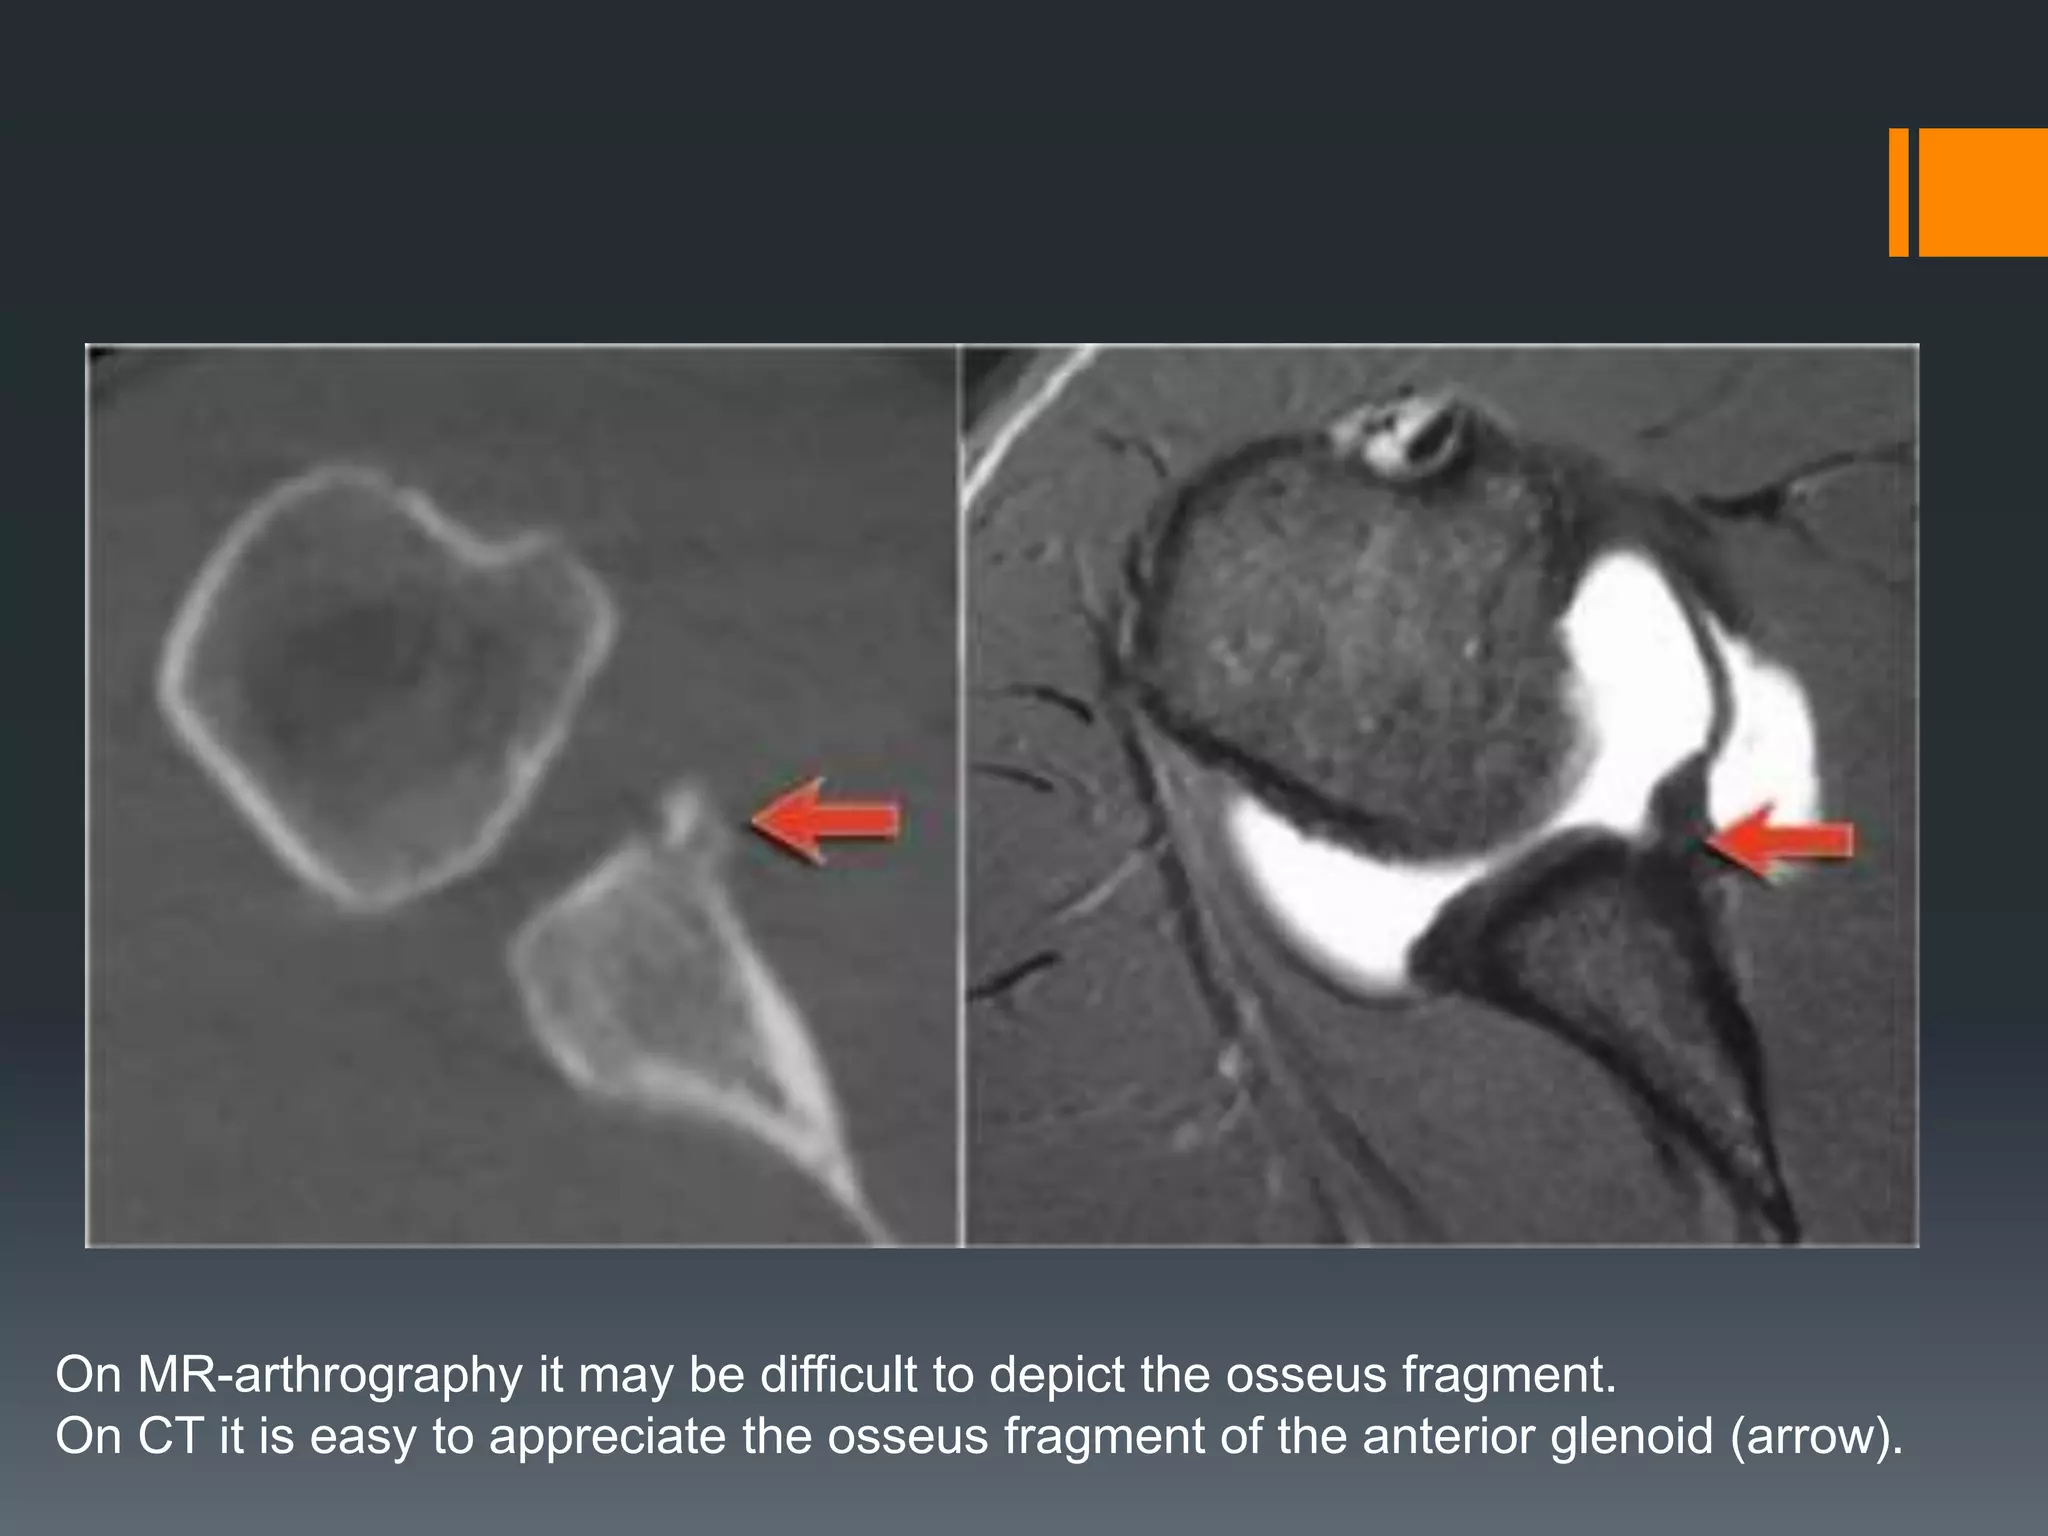

Osseus Bankart

Bankart lesions with an osseus fragment are common findings in patients with an

anterior dislocation and are frequently seen on the x-rays or CT-scan.

On MR-arthrography it may be difficult to depict the osseus fragment.

On CT it is easy to appreciate the osseus fragment of the anterior glenoid (arrow).